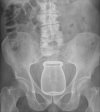

Man (88) arriveert in ziekenhuis met bom uit Eerste Wereldoorlog in anus![]()

Man (88) arriveert in ziekenhuis met bom uit Eerste Wereldoorlog in anus

Er was afgelopen zaterdag een bommelding in een ziekenhuis in Frankrijk toen een 88-jarige Fransman arriveerde met een twintig centimeter langewww.waterkant.net

tis maar een bierflesje, wacht maarrrrr...bijna nieuwjaarEven eerlijk, jij kan zo’n fles ook wel hebben toch?

Wat zit jij nou weer te brabbelen?tis maar een bierflesje, wacht maarrrrr...bijna nieuwjaar![]()

Met oud en nieuw gaat ie een bompijl laten verdwijnen.